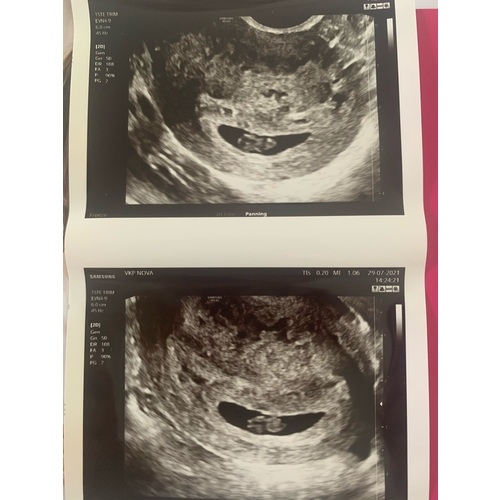

8 weken ongeveer uitwendige echo.. kan er zelf echt niks van maken🥲😂

Ik denk een 💙 maar is wel een lastige